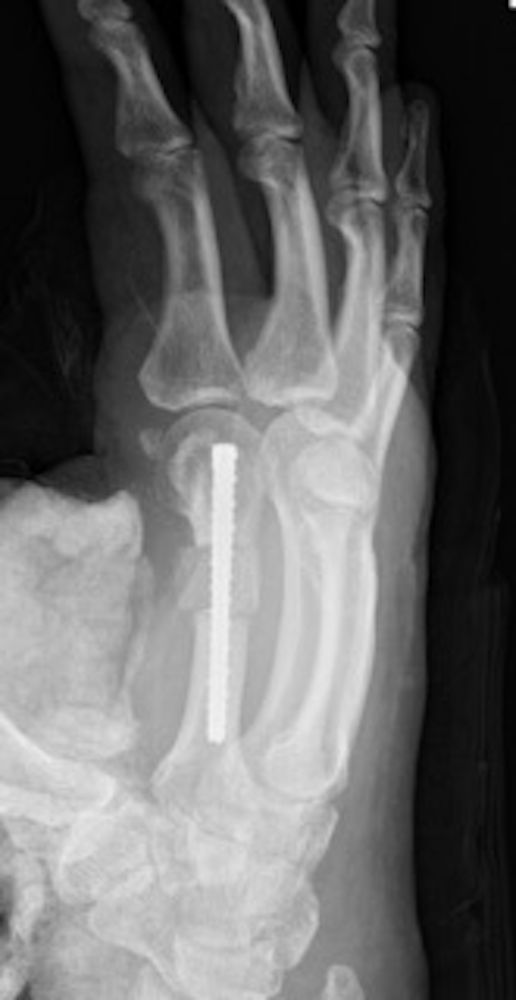

The patient was seen 2 weeks postoperatively and sutures and splint were removed. He was enrolled in occupational therapy to work on active and passive range of motion. He was seen again at 6 weeks and 3 months postoperatively. The graft site incorporated well with robust callus formation with mild resorption and collapse (Figures 8 and 9). At the time of surgery, a 50-mm screw was chosen based on intraoperative measurements. In hindsight, a longer screw could have been utilized. Clinically he maintained appropriate rotation and had a 5-degree extensor lag with the ability to make a composite fist (Figures 10 and 11). The patient was satisfied with his result and returned to normal activities with no restrictions at 3 months and was advised to return to clinic as needed.

Figure 9. Six-week postoperative lateral X-ray of healing index finger metacarpal osteotomy, cortical bone graft, and compression screw.